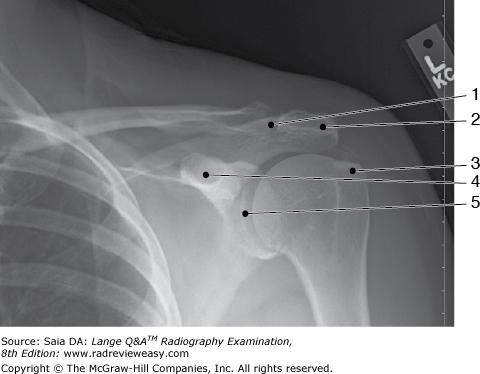

In which position of the shoulder is the outline of the greater tubercle superimposed on the humeral head?

D Neutral position

-The external rotation position is the true AP position and places the greater tubercle in profile laterally and places the lesser tubercle anteriorly. The internal rotation position demonstrates the lesser tubercle in profile medially and places the humerus in a true lateral position; the greater tubercle is seen superimposed on the humeral head. The epicondyles should be superimposed and perpendicular to the IR. The neutral position places the epicondyles about 45 degrees to the IR and the outline of the greater tubercle superimposed on the humeral head.